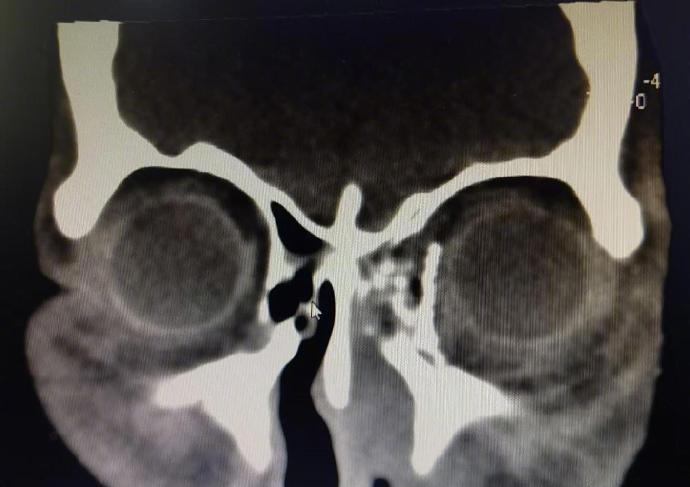

綜合《貴州日報》、《北京日報》等內地媒體報道,貴州醫科大學附屬醫院創傷科近日接獲一宗特殊病例,病者為一名50歲女子,因一腳踩空不慎從3樓墜落,導致全身多處疼痛及左眼視力喪失,被送往該院救治。經檢查後,發現病者的左眼球脫位,並嵌頓於鼻腔內,情況十分危急。經過近4個小時的緊張手術,眼球成功復位到左眼眶內,並修得了眼眶爆裂性骨折。由於手術採取了微創手術切口,病者的外觀並未留下手術疤痕。術後第一天,病者的左眼便恢復光感,這意味著她的左眼視功能得以保留,為今後的康復創造了條件。